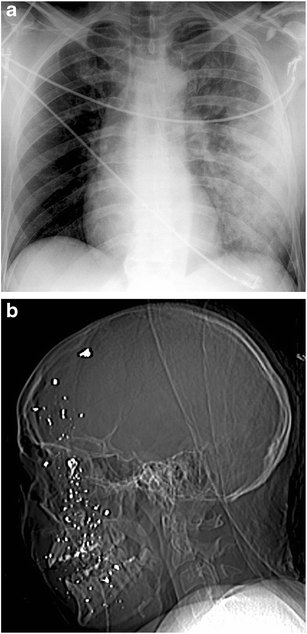

Imaging of two patients in the emergency department. a Plain film of the chest of a patient with blast injury to the upper left chest causing pulmonary contusion, comminuted fracture in the lateral part of the clavicle and multiple rib fractures. b CT scout of patient from the shooting incident with fragmenting injury to the face and head